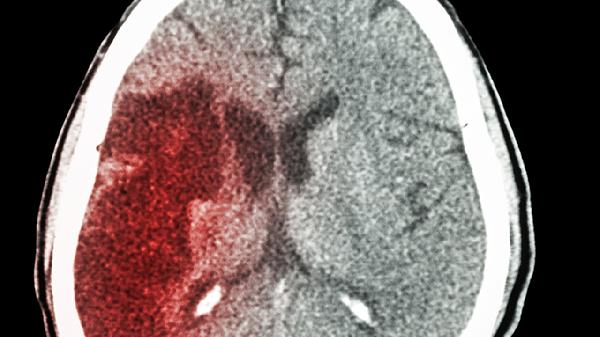

胎儿颅内出血常见于血小板减少症、血管畸形或外伤等情况。出血形成的血块可能阻塞导水管或蛛网膜下腔,血液分解产物还会刺激脑脊液分泌增加。孕晚期出血可通过超声观察到脑室内强回声团块。轻度出血可能自行吸收,严重出血需产后评估是否需脑室引流。孕妇补充维生素K有助于预防出血性疾病相关脑积水。